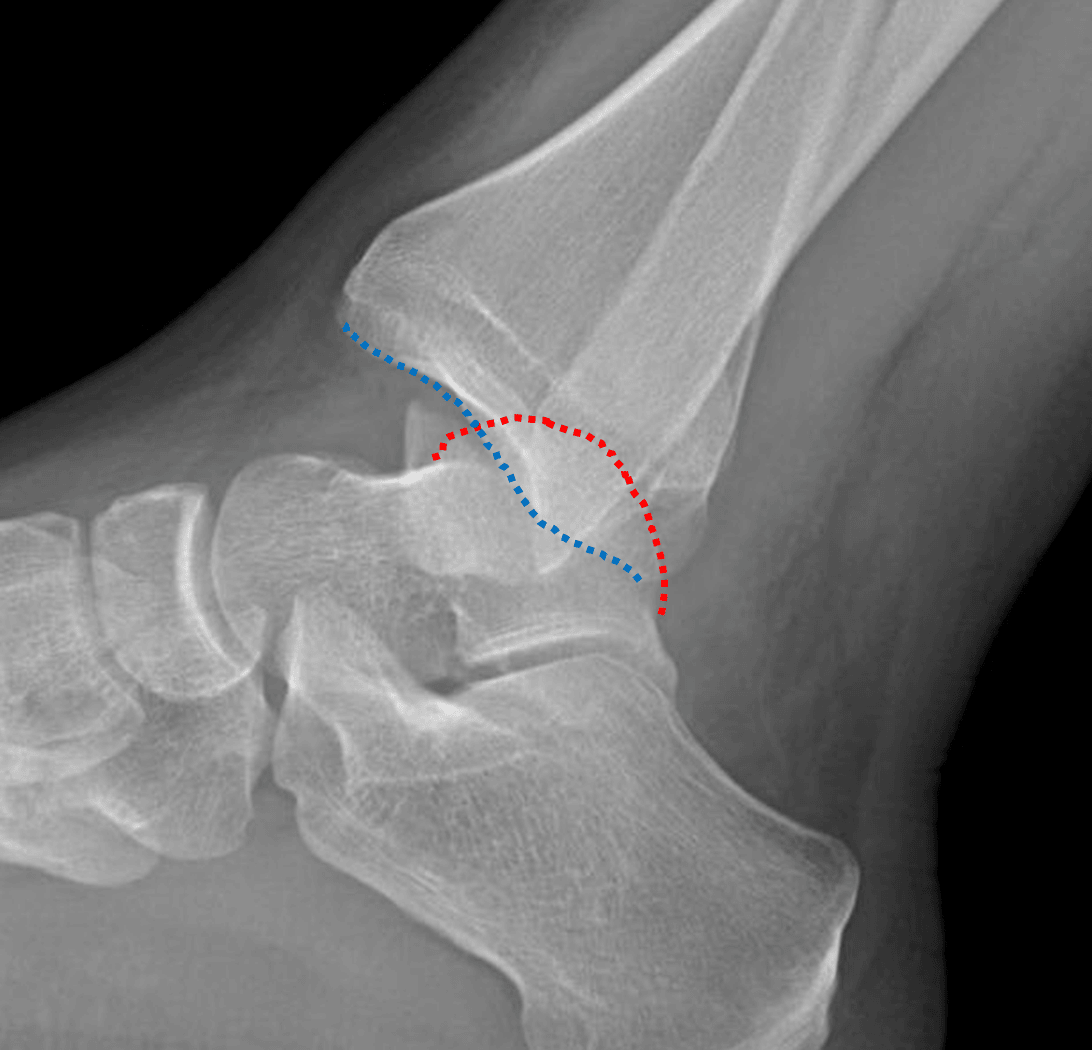

Posterior dislocation of the ankle with the talar dome (red dotted line) positioned posterior to the tibial plafond (blue dotted line).